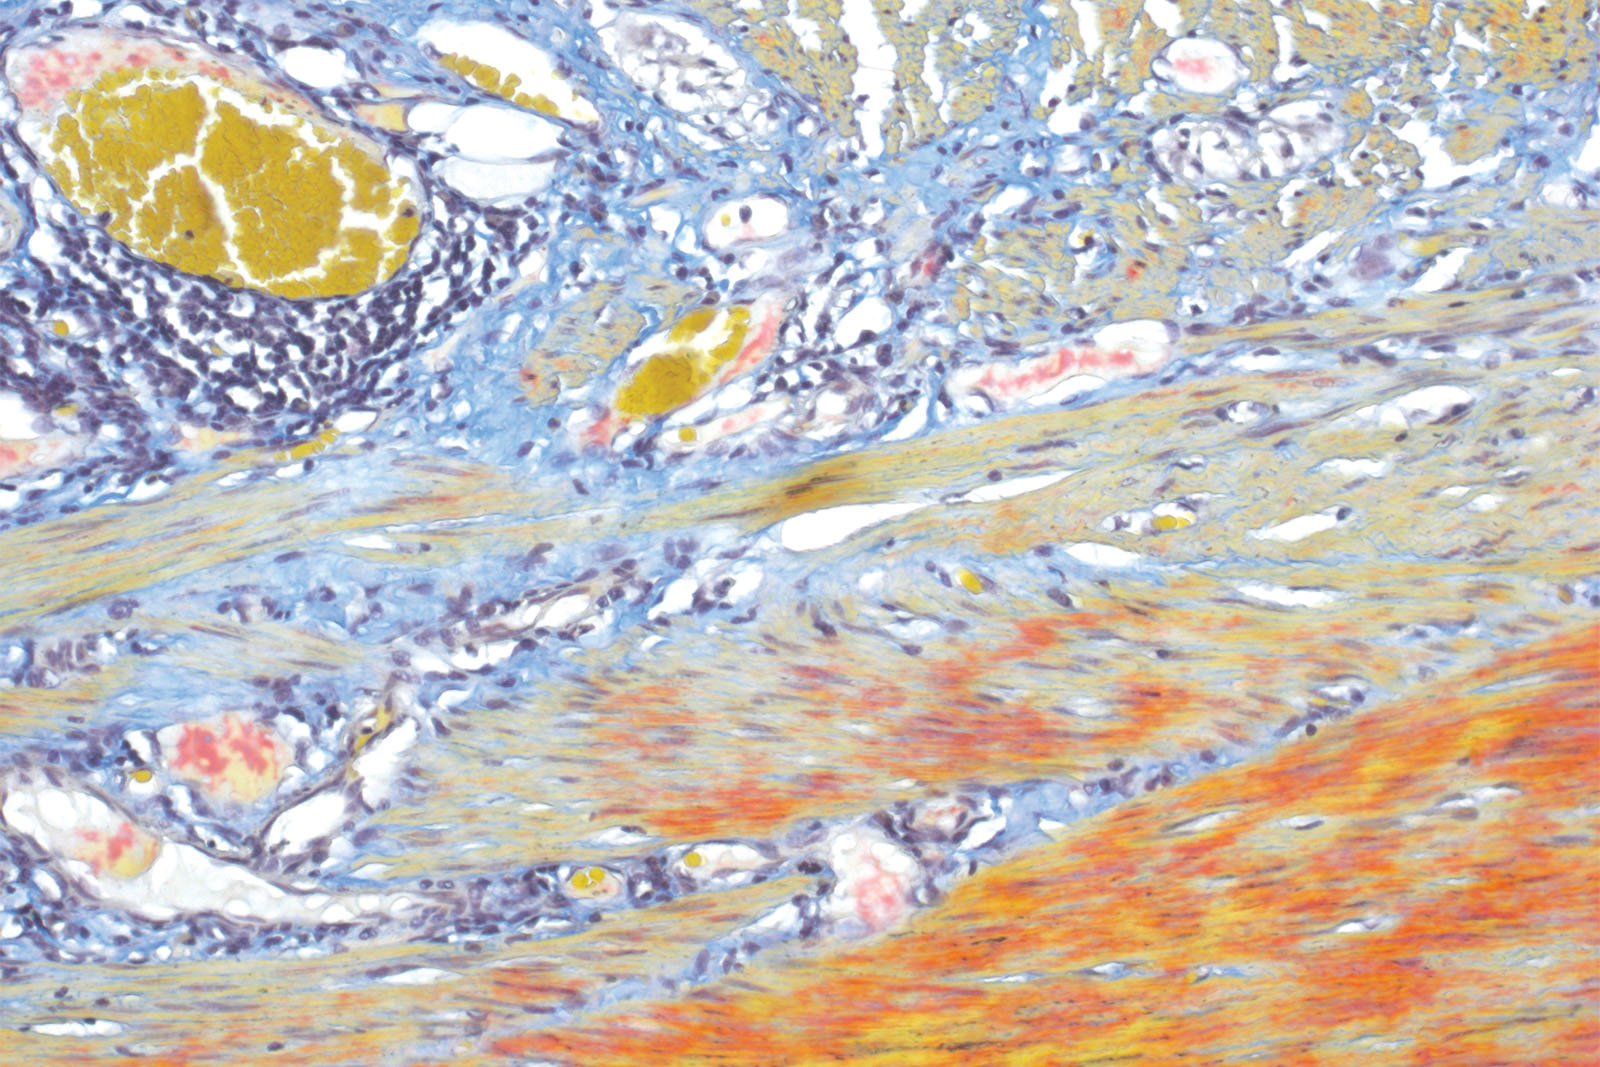

Histology, cytology and other related scientific disciplines study the microscopic anatomy of tissues and cells. In order to demonstrate a good tissue and cellular structure, the samples need to be stained in a correct manner. Martius Scarlet Blue (MSB) staining technique is used for fibrin visualization, especially of older clusters. This method is a modified Masson Trichrome method and it is ideal for studying connective tissue and vascular pathology.